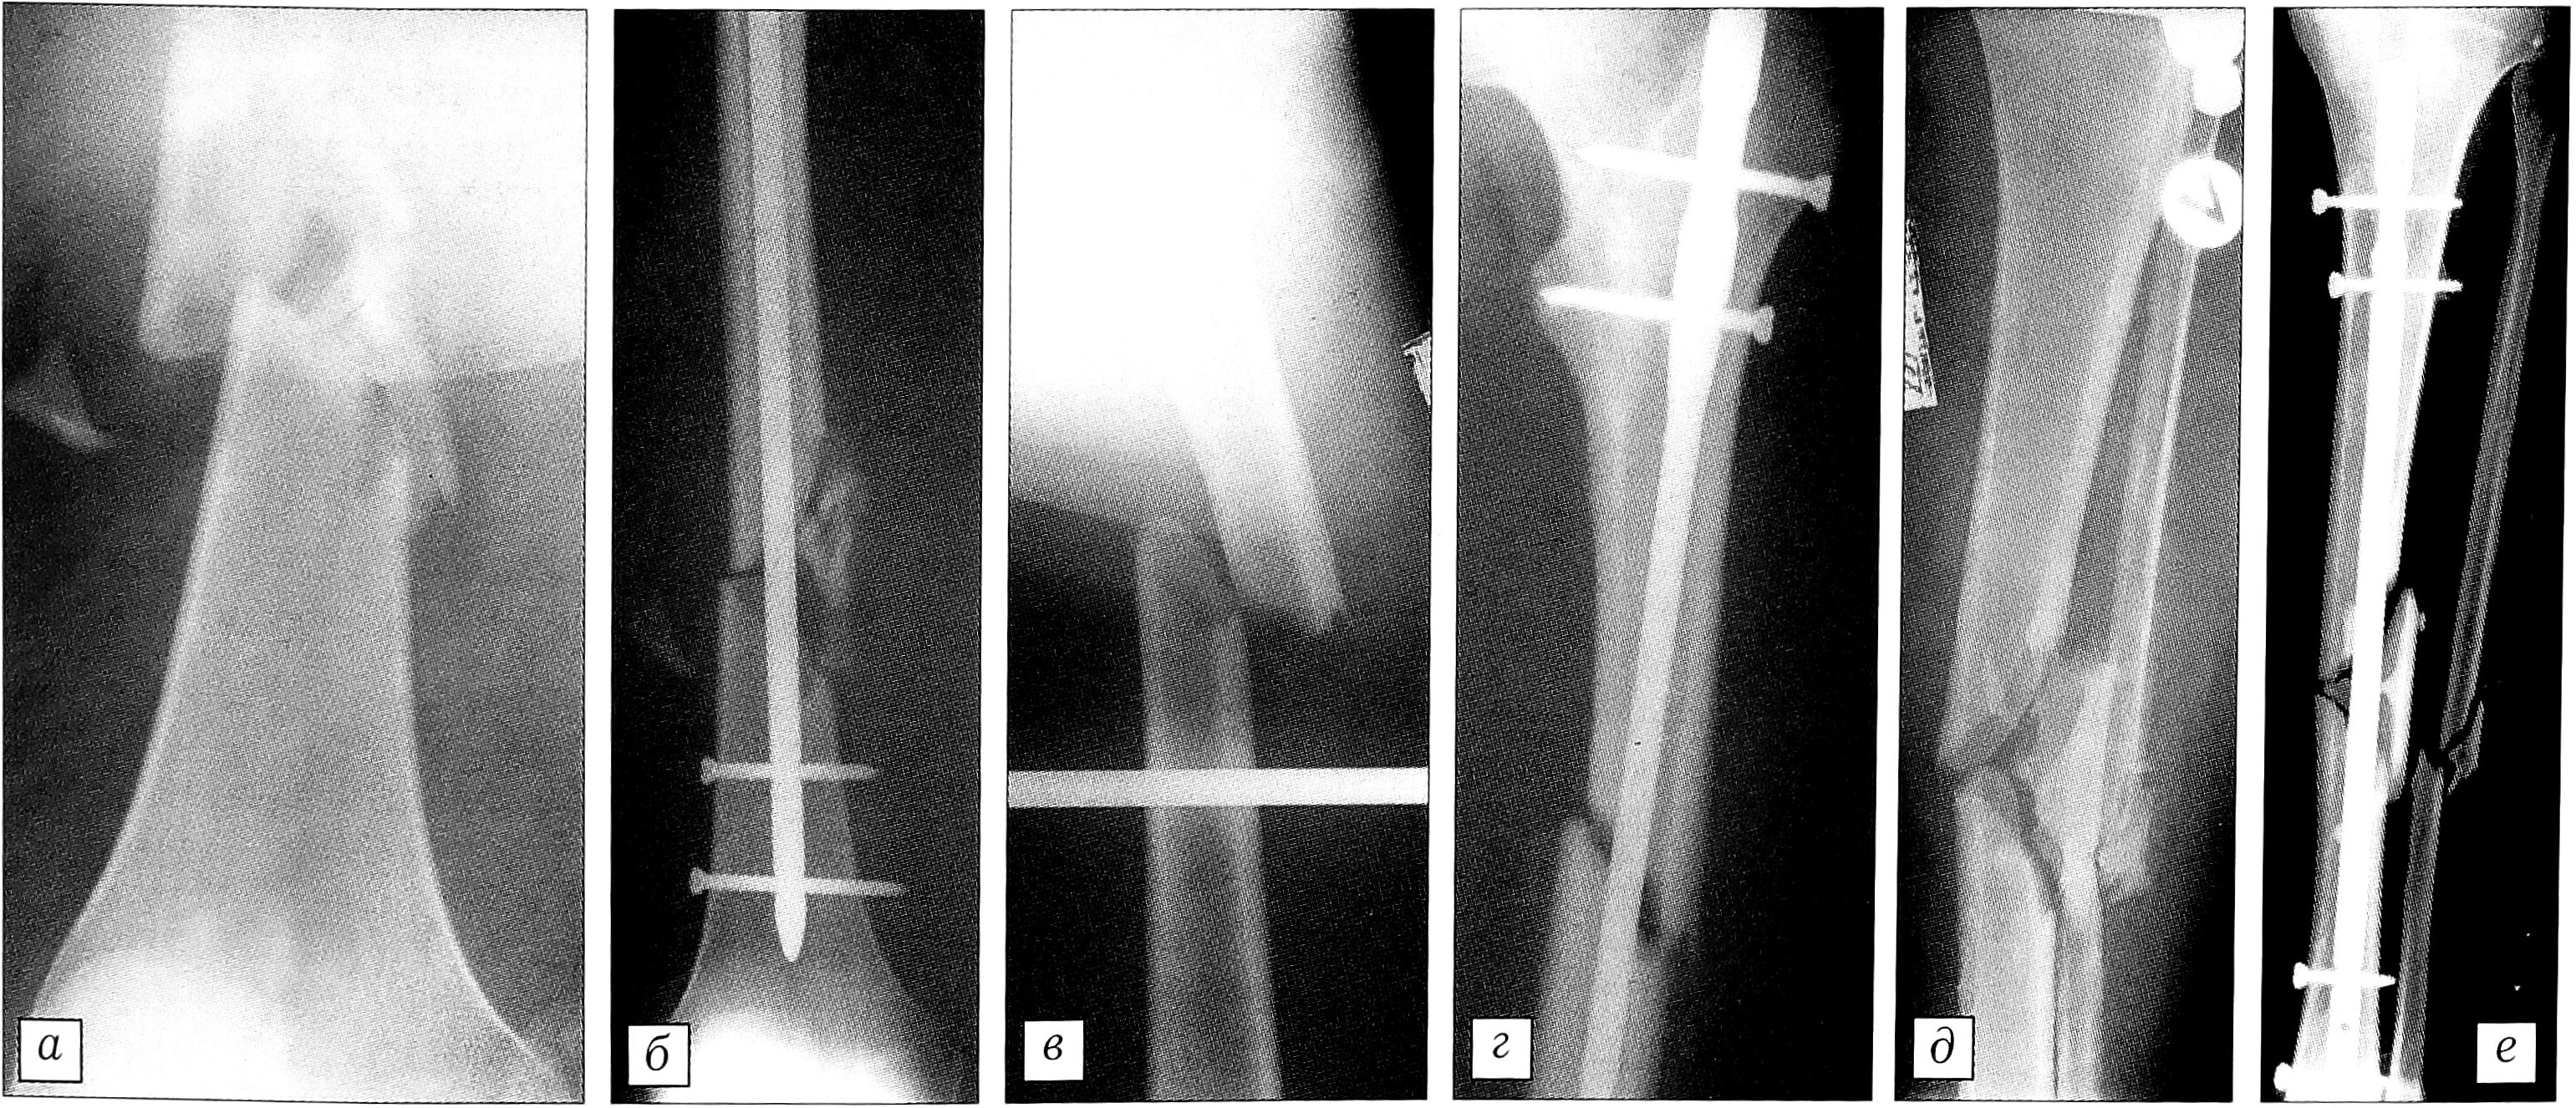

Выбор метода остеосинтеза зависел от характера перелома и тяжести состояния пострадавшего. В случаях простых и оскольчатых переломов типа А и В наилучшие результаты получены при открытом остеосинтезе штифтом (29 операций), а также при интрамедуллярном остеосинтезе штифтом с дополнительной стабилизацией места перелома пластиной (9 операций) (рис. 1). Накостный остеосинтез пластинами АО применялся при простых и оскольчатых переломах у больных с сочетанной травмой груди, а также при сочетании диафизарного перелома с внутрисуставным или мета- физарным переломом того же сегмента конечности (24 операции). Выполнение погружного остеосинтеза было возможно при тяжести полученных повреждений по шкале ISS < 25 баллов.

Рис. 1. Рентгенограммы больного А. Оскольчатый перелом бедра типа В. а — до операции; б — после остеосинтеза штифтом и дополнительно пластиной.

Клинический пример. Больной Л.,23 лет, поступил в реанимационное отделение НИИ СП им. Н.В. Склифосовского через 1,5 ч с момента получения травмы (попал в автоаварию, находясь за рулем мотоцикла). В результате обследования поставлен диагноз: сочетанная травма, сотрясение головного мозга, перелом VI—VII ребер справа с повреждением ткани легкого, правосторонний пневмоторакс, закрытый оскольчатый перелом правого бедра (тип В по классификации АО), закрытый перелом левого бедра (тип А), закрытый оскольчатый перелом левой голени (тип В) (рис. 2, а, в, д). При поступлении больному проводились противошоковые мероприятия, в том числе анестезия мест переломов, дренирование правой плевральной полости; для иммобилизации переломов бедер и голени было наложено скелетное вытяжение. На 5-е сутки дренаж из плевральной полости удален. На 10-е сутки под спинномозговой анестезией произведен одномоментно закрытый блокирующий остеосинтез обоих бедер и левой большеберцовой кости гвоздями без рассверливания костномозгового канала (рис. 2, б, г, е). Перед операцией НЬ 87 г/л, Нt 29%. Во время операции переливались свежезамороженная плазма (725 мл) и эритроцитная масса (200 мл). После операции НЬ 92 г/л, Ht 30%. Ранний послеоперационный период протекал без осложнений. Движения в смежных суставах начаты на 3-й день после операции. Швы сняты на 12-е сутки. Заживление послеоперационных ран первичным натяжением. Через 13 дней после операции у больного выявлен окклюзионный тромбоз общей бедренной вены слева. Проводилась консервативная терапия. Через 48 дней после операции больной активизирован — начал вставать и учиться ходить с дополнительной опорой на костыли. На 63-й день после получения травмы пациент выписан на амбулаторное лечение в удовлетворительном состоянии, с полным восстановлением движений в суставах конечностей.

Рис. 2. Рентгенограммы больного Л. Оскольчатый перелом правого бедра (а — при поступлении, б— после закрытого остеосинтеза с блокированием); перелом левого бедра (в — при поступлении, г — после закрытого остеосинтеза с блокированием); оскольчатый перелом костей левой голени (д — при поступлении, е — после закрытого остеосинтеза с блокированием).